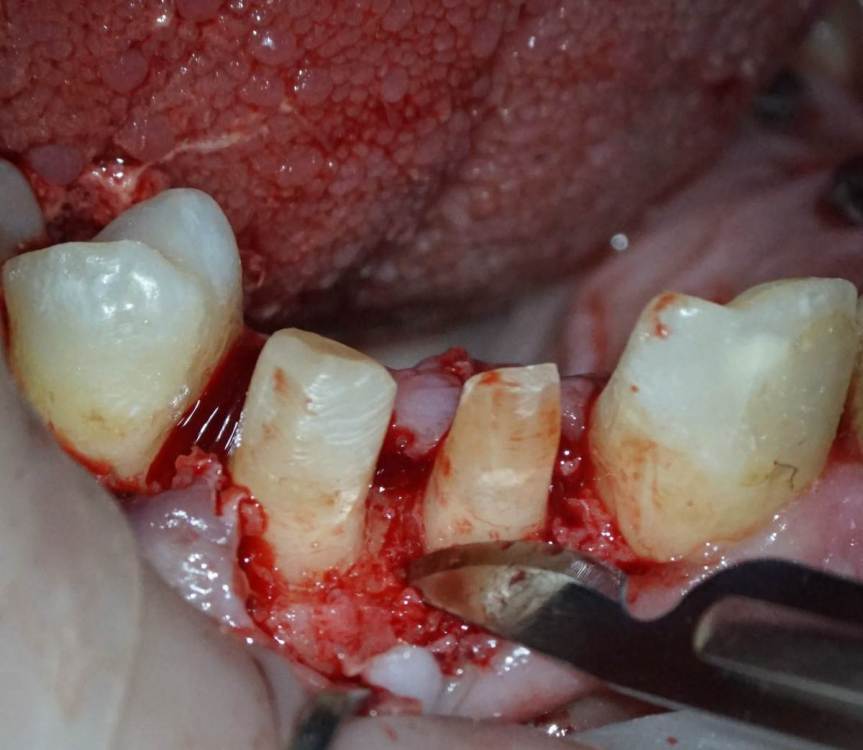

TIGER Опубликовано 3 ноября, 2023 Поделиться Опубликовано 3 ноября, 2023 Периохирургия способна на чудеса)не спешите удалять зубы 5 1 Ссылка на комментарий